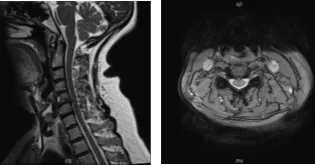

El paciente presentó resultados para la resonancia magnética en la columna cervical y mostró hernias discales posteroventrales en C4-C5 y C6-C7, que hendieran el saco tecal ventral y la superficie de la médula ventral. Bulto anular/espolón vertebral en C5-C6, asociado a espolón bilateral uncovertebral, ligeramente mayor en el lado derecho.

Los hallazgos resultan en un efecto masivo sobre el saco tecal y la médula espinal, una invasión foraminal bilateral y un ligero empeoramiento en la derecha. Estenosis cervical espinal leve. Artropatía facetaria en la región cervical superior, más marcada en la izquierda.

Resonancia magnética de columna cervical sin contraste